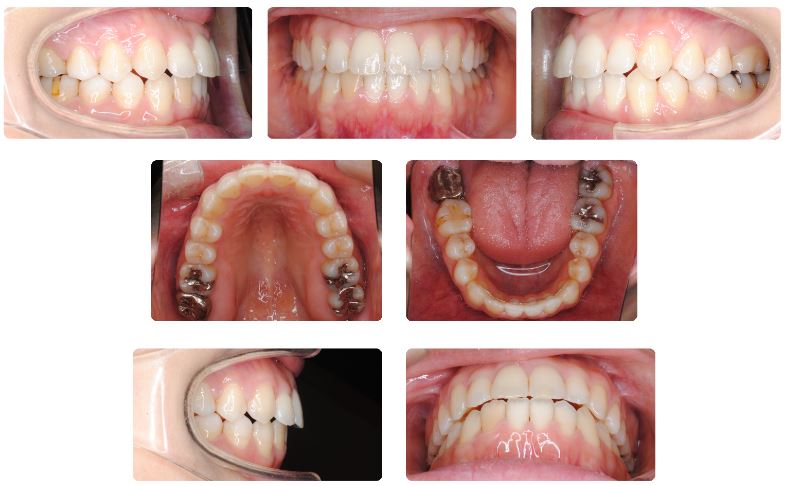

治療期間は1年3ヶ月でした。

再治療ですので、前歯部開咬の再発防止のためMFTによる舌の挙上トレーニングを徹底して、前歯の咬みあわせを深めに仕上げたうえで咬み合わせが安定したところで動的処置を終えました。